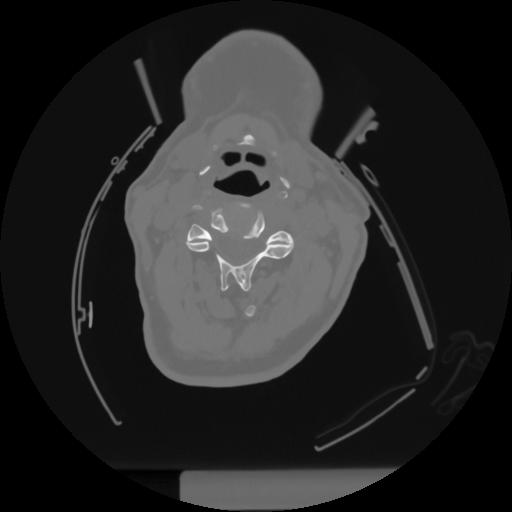

12 P.BLANDAS,,Vol,0.5,P.BLANDAS,,